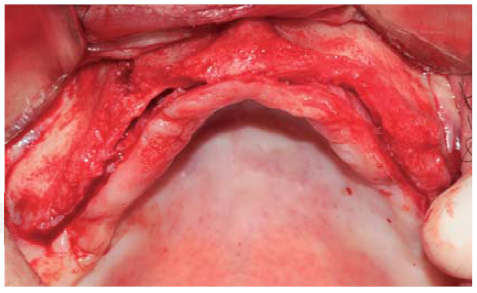

Se realizó una incisión supracrestal a espesor total, elevación del colgajo mucoperióstico exponiendo la tabla ósea hasta 4 mm de la cima de la cresta hacia vestibular y desde ese punto se dividió el colgajo a espesor parcial (Figura 3). Luego se marcaron los puntos de impacto en los sitios designados según la guía quirúrgica para la colocación de los implantes y se iniciaron las perforaciones con una fresa de 1.6 mm de diámetro para determinar el eje y profundidad deseada para los implantes. Luego se procedió a crear un surco a nivel crestal con un disco de diamante rompiendo el hueso cortical para crear el acceso a los escoplos al hueso esponjoso y con éstos se procede a separar las tablas óseas hasta llegar a una profundidad de 5 mm (Figuras 4 y 5). Seguidamente, se continuaron las perforaciones con una fresa de 2.0 mm de diámetro (Figura 6) y se realizó la expansión de la tabla vestibular creando una fractura en tallo verde con los expansores hasta alcanzar el diámetro del lecho óseo suficiente para poder utilizar la última fresa de 3.2 mm de diámetro (Figuras 7 y 8). Posteriormente, se colocaron los implantes a una velocidad de 25 rpm y a un torque de 35 Ncm (Figuras 9 y 10). Seguido de esto, se colocó un injerto óseo bovino particulado (Bonefill® Bionnovation Biomedical, Sao Paulo-Brazil), con la finalidad de preservar la integridad de las tablas óseas vestibulares (Figura 11). Todos estos procedimientos, se realizaron de la misma manera para la colocación de los seis implantes. Finalmente, se suturó con nylon monofilamento 5/0.

Figura 4 Disco de diamante de 0.5 mm de grosor utilizado para crear el surco crestal atravesando el hueso cortical permitiendo el acceso para el cincel óseo.

Figura 5 Cincel óseo ingresando a la porción medular, separando el reborde cortical llevando a una fractura en tallo verde.